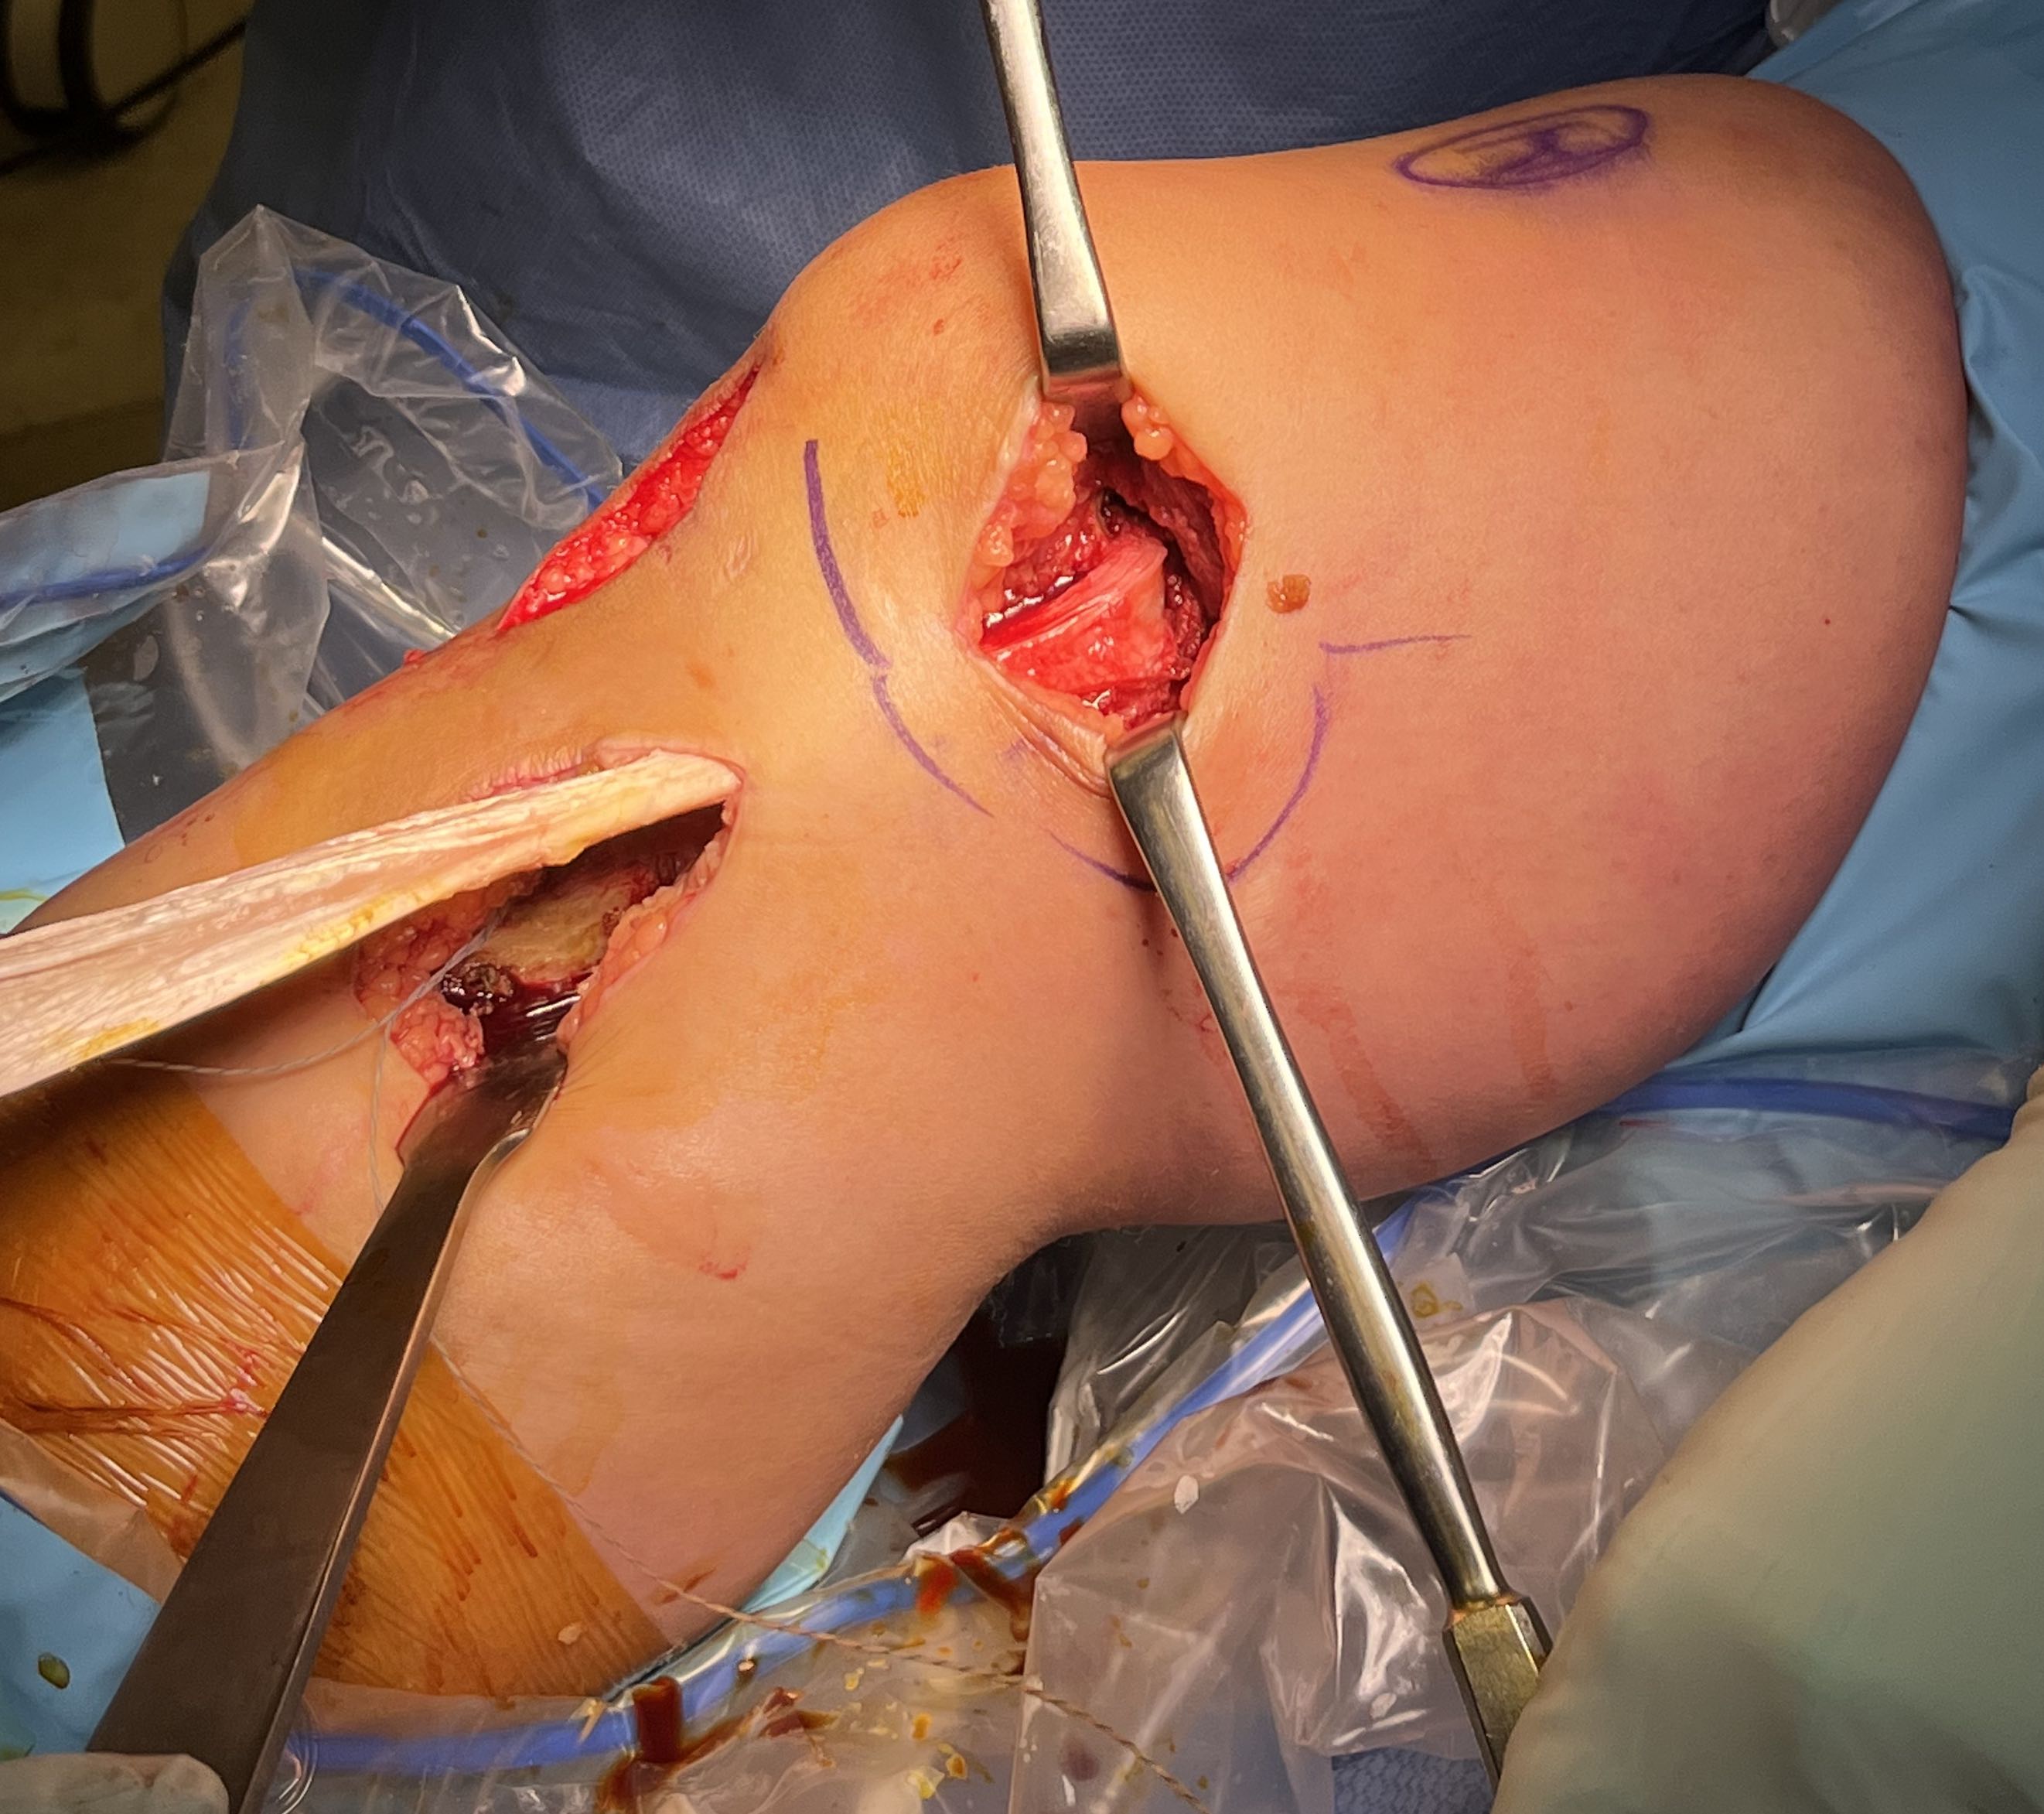

Surgical Approach to Medial Knee

Position

- knee flexed to 90o, over bolster

- tourniquet

- sandbag under hip

Incision

- hockey stick medial incision

- halfway between borders of tibia

- extends proximally to adductor tubercle

- distally to pes anserinus

Superficial dissection

- protect the saphenous nerve and small saphenous vein

- emerges from between sartorius and gracilis

- divide medial patella retinaculum from VMO down

- divide sarfascia over pes anserinus

- reflect pes anserinus inferiorly

Deep dissection

- elevate VMO to identify proximal insertion of superficial MCL

- expose superficial MCL running from medial epicondyle down to tibia under pes

- popliteal oblique ligament and semimembranosus are posterior to MCL

- can expose posterior capsule by carefully reflecting medial gastrocnemius posteriorly